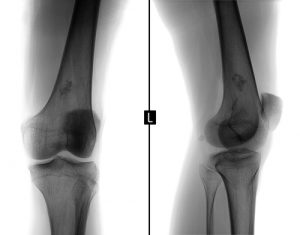

- Рентгеновская диагностика.

Саркомы костей

Наиболее эффективный вид лечения заключается в хирургическом удалении новообразования. В зависимости от локализации опухоли, могут проводиться различные виды резекции. Если новообразование обнаружено на ранней стадии, врач удаляет лишь опухоль вместе с частью окружающих ее здоровых тканей. На поздних стадиях могут потребоваться более объемные виды операций. Часто используется блочная резекция. Современные виды хирургии позволяют сохранить до 90% конечности и эффективно удалить опухоль. Израильские врачи выполняют щадящие операции, сохраняя максимально возможный объем здоровых тканей, чтобы обеспечить высокое качество жизни пациента.